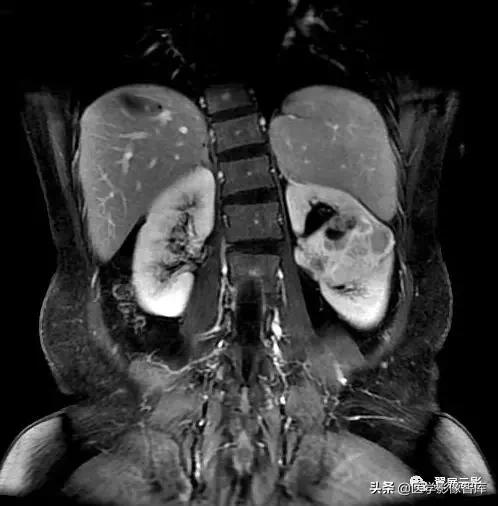

嗜铬细胞瘤

本病由嗜铬细胞组成,常位于肾上腺髓质,多为单侧性,也可见于双侧,在成人90%位于肾上腺,肾上腺以外的嗜铬细胞瘤常在腹膜后沿交感神经链分布,此瘤多见于成人,此瘤因分泌儿茶酚胺,肾上腺素与甲基肾上腺素而产生阵发性高血压为典型临床表现,MRI横断面结合冠状面扫描对于发现肿瘤和定性诊断有很大价值。

注意观察描述嗜铬细胞瘤的特征:T1WI低或等信号,T2WI信号显著增高,瘤周常有低信号包膜,瘤内信号均匀或不均匀,坏死囊变区T1低信号T2高信号,合并出血T1,T2呈片状高信号,双侧性嗜铬细胞瘤并不少见,注意恶性嗜铬细胞瘤和异位嗜铬细胞瘤的情况。